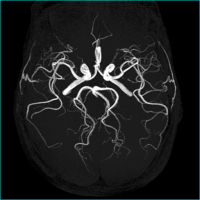

Q.レビー小体型認知症とはどのようなものですか?

レビー小体型認知症とは、脳の中にレビー小体というものがたまってきて物忘れ症状をきたす病気の一つです。物忘れ以外にも、パーキンソン病様の症状、幻視、妄想、アパシー、転倒や失神、レム睡眠期行動異常症などをきたすことがあります。

パーキンソン病でも症状が進行してくると認知障害が認められてきますが、本質的には同じグループの疾患ではないかと考えられています。

Q.認知症の原因にはどのようなものがありますか?

アルツハイマー型認知症、Lewy小体型認知症、前頭側頭型認知症、血管性認知症などがあります。その他、正常圧水頭症、慢性硬膜下血腫、脳腫瘍など手術することでよくなる認知症もあります。その他内科的には、甲状腺機能低下症、臓器不全、睡眠薬の副作用などでも認知症様の症状をきたすことがあります。